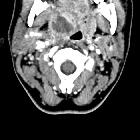

CT

- rim-enhancing fluid collection adjacent to an enlarged and inflamed tonsil

- 75% specific and 100% sensitive at diagnosing peritonsillar abscess

- false positives are due to the similar appearances of peritonsillar abscess and phlegmon